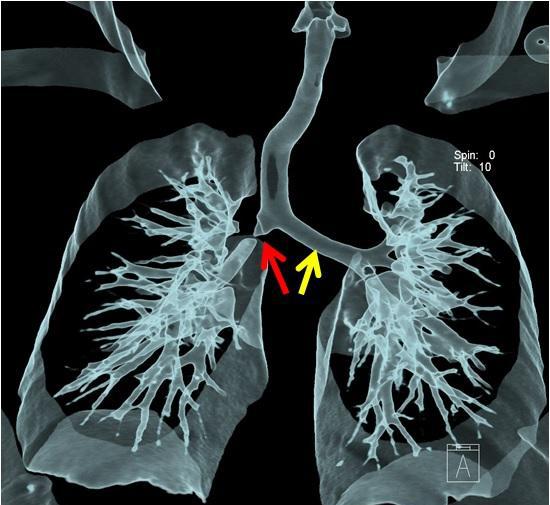

6. 空气支气管征:细条状,直径约 1 mm 的空气密度影.

可见深浅不一的分叶,兼有多个征象恶性,细支气管充气征及支气管截断征